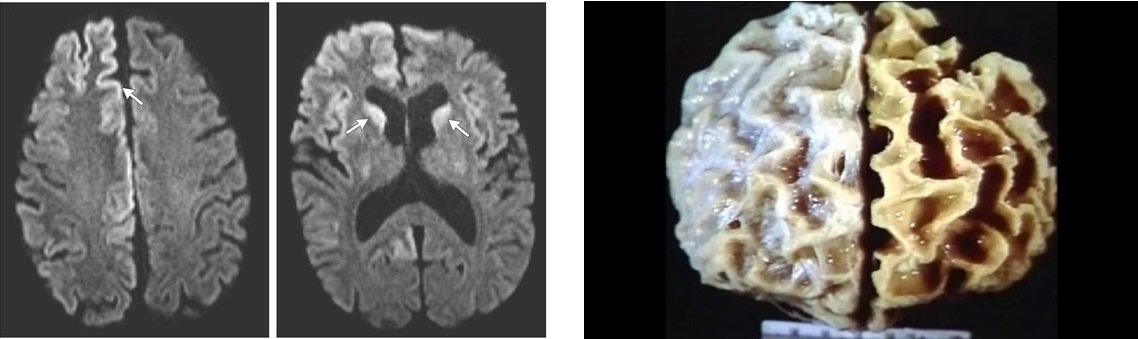

Vamos começar com a doença de Creutzfeldt-Jakob

A primeira doença que vou comentar neste artigo é a mais sinistra desta lista, pois é rara, degenerativa e fatal. Segundo estudos, é iniciada pela transmissão de uma proteína chamada príon. Esta proteína afeta o sistema nervoso central e desencadeia perda de memória, convulsões, paralisia facial, problemas motores e rigidez muscular. Segundo estudos, sua incidência é de 1 em cada milhão de habitantes.

O maior risco são pessoas entre 40 e 70 anos.

A doença de Creutzfeldt-Jakob foi descrita pela primeira vez na década de 1920 por neurologistas alemães e infelizmente, ainda não existe uma cura dada a complexidade de sua ação (ver imagem abaixo). Após o diagnóstico, o tratamento também não é eficaz e os afetados costumam falecer após um ano do surgimento dos sintomas e confirmação do diagnóstico. Existe ainda uma variante dessa patologia, capaz de atingir pessoas mais jovens e é conhecida como “doença da vaca louca”. Acredito que muitos leitores já ouviram falar e com isso temos uma impressão melhor desta doença cruel.